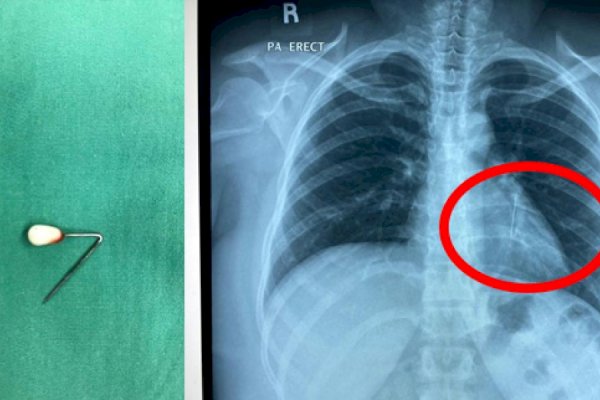

Pedomanrakyat.com, Jakarta – Viral di media sosial momen dokter mengeluarkan jarum pentul dari lambung. Jarum pentul itu disebut tertelan saat pasien hendak memakai hijab.

Operasi tersebut dilakukan oleh spesialis penyakit dalam Prof dr Ari Fahrial Syam, SpPD juga dekan Fakultas Kedokteran Universitas Indonesia (FKUI). Dalam unggahannya, dia menyebut jarum pentul dikeluarkan lewat metode endoskopi.

“Alhamdulullah jarum pentul yang sudah tertanam beberapa hari bisa dikeluarkan dari lambung tanpa operasi. Pelajaran buat yang masih menggunakan jarum pentul buat hijab jangan menggigit jarum saat mau pasang hijab,” tulis dr Ari dalam unggahannya dikutip detikcom atas izin yang bersangkutan, Senin (16/9/2024).